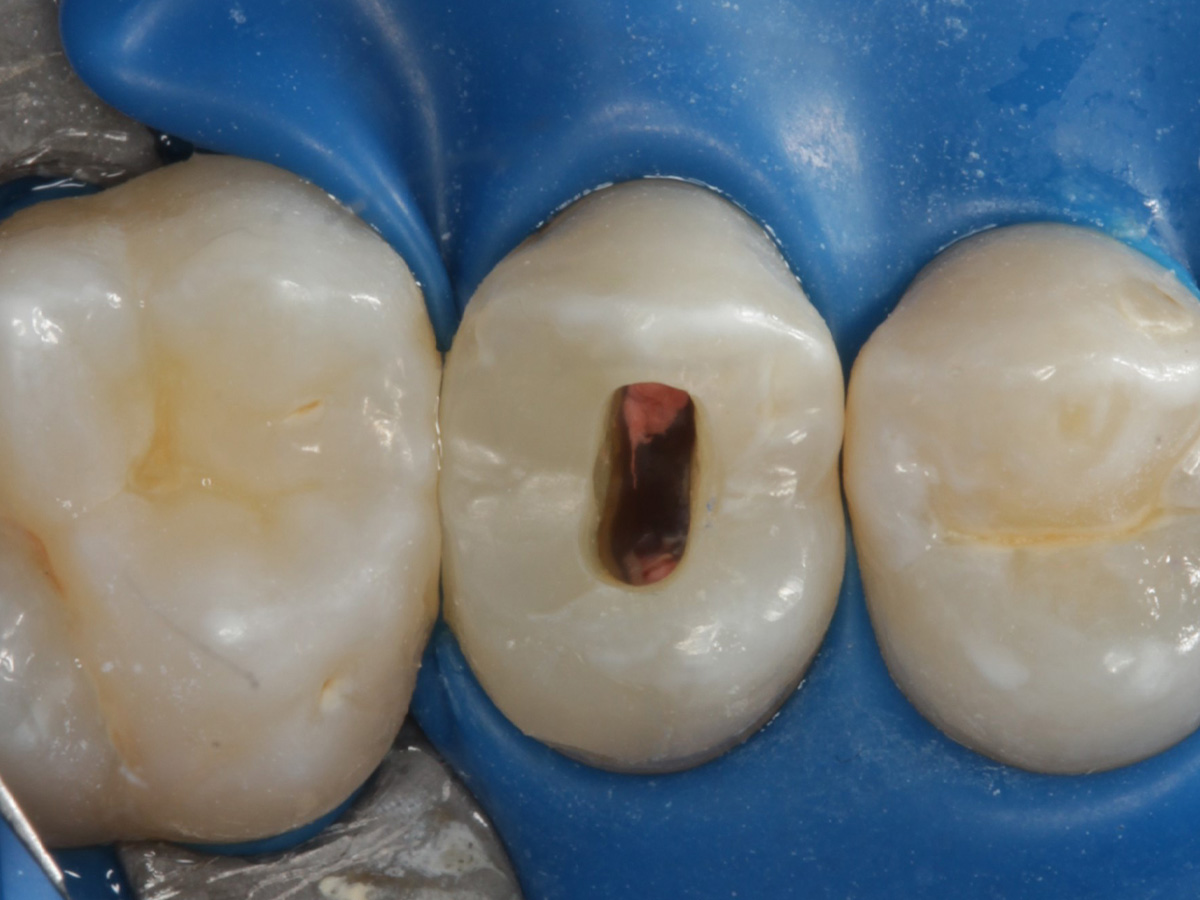

Abbildung 5

Height Indicator vor Auswahl der passenden Evolve Matrize nach Defektdarstellung, Kariesexcavation, Vitalexstirpation